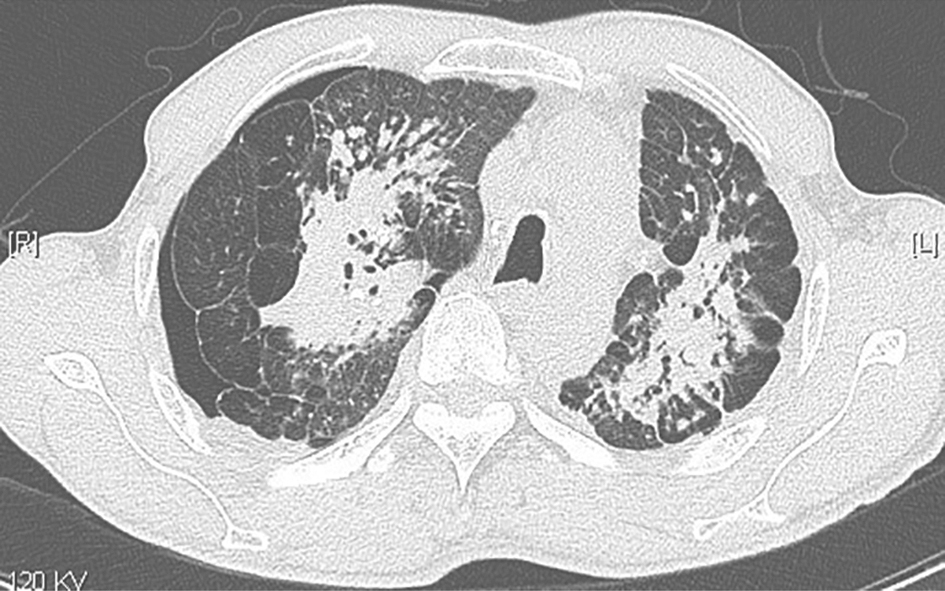

图3尘肺合并右侧气胸胸部CT表现

胸部CT可见双肺中上肺为主的高密度实变影,肺内结节影伴小叶间隔增厚,间隔旁肺气肿,右侧少量气胸,双侧胸膜肥厚